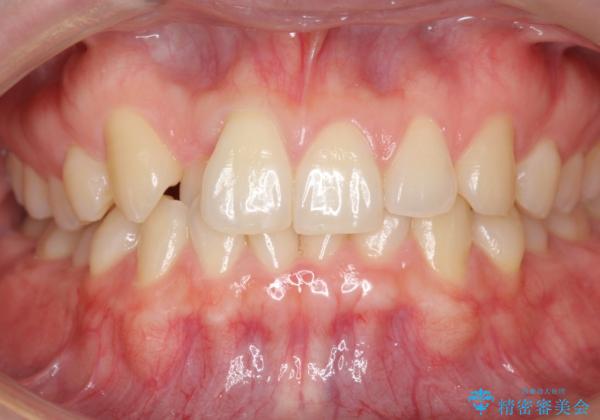

- 右上の前歯が内側に入っているのを気にして来院。

右上の奥歯を後ろに移動して、前に出すスペースを確保してから並べました。

前歯が内側に入っていると、笑った時にそこが黒くなり、歯が抜けたように見えます。

口を開けたとき、笑顔の印象が大きく変わり、大変喜んでいただけました。